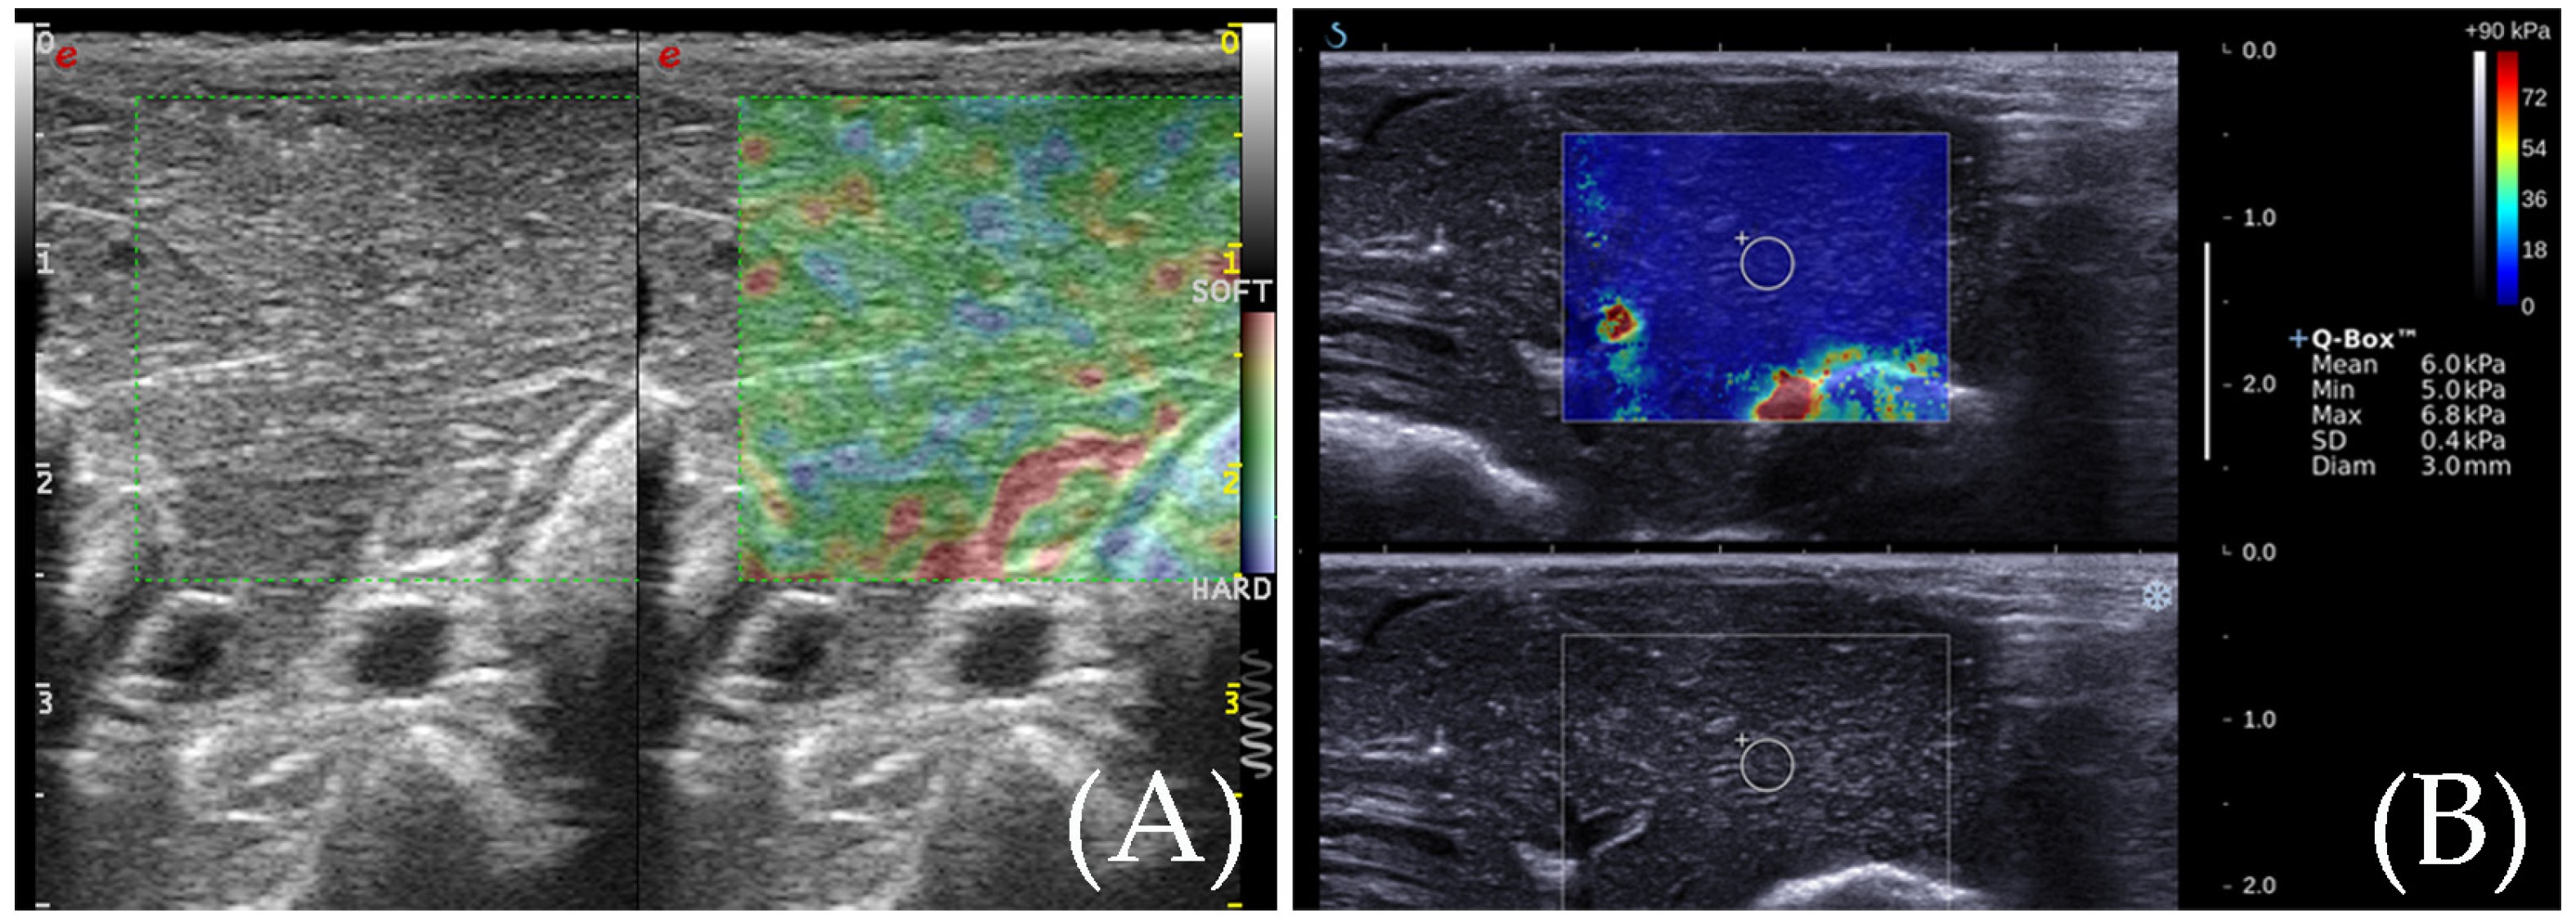

The RTE images showed that the ablation zone had a clear boundary, and was indicated by a homogeneous blue, while the surrounding normal liver tissue was indicated by yellow, green, and red colors (Figure 3). For RFA, the ratio of the elastic value of the ablation zone rim to the surrounding normal liver tissue was 3.41 ± 0.67 (2.23–4.76). The area of the ablation zone measured by RTE was 1.089 ± 0.199 cm2 for RFA.

3.3. SWE for the Detection of the Ablation Zone

From SWE, we can also see the ablation zone had a clear boundary. The ablation zone showed a yellow–green–red tricolor change, and the surrounding normal liver tissue showed a uniform blue color. A 2 mm sampling frame was used to measure the elasticity of the ablation zone from the center to the periphery, and the changes in Young’s modulus values were analyzed. The Young’s modulus gradually decreases from the center of the ablation zone to the periphery (Figure 3). The Young’s modulus within the RFA ablation zone ranged widely from 33.2 to 70.4 kPa (50.7 ± 11.3 kPa), while the Young’s modulus at the edge of the ablation zone ranged from 25.1 to 36.3 kPa (28.5 ± 3.13 kPa) which was relatively stable. The area of the ablation zone was 1.059 ± 0.201 cm2 for RFA based on elastic images.

3.4. Contrast-Enhanced Ultrasound Examination

After the elastic examination, a CEUS examination was performed for the ablation zones of New Zealand rabbits. It indicated no enhancement during the entire period (Figure 3). The surrounding normal liver tissue indicated uniform iso-enhancement performance. The average area of the ablation zone was 3.091 ± 0.591 cm2 for RFA.

3.5. Gross Specimen Observation and Comparison of the Three Imaging Methods

Figure 3. (A) RTE elasticity image of the ablation zone. The even blue indicates the ablation zone, and its boundary is clear. The yellow, green, and red indicate the peripheral normal liver. (B) The diameter of the ablation zone was measured according to the elasticity image. (C) SWE elasticity image of the ablation zone. The ablation zone is indicated by three colors: yellow, green, and red. The peripheral normal liver is indicated by an even blue color. (D) The diameter of the ablation zone was measured according to the elasticity image. (E) After CEUS, the diameter of the ablation zone was measured by CEUS image. (F) The gross specimen of the ablation zone was measured after sacrifice.